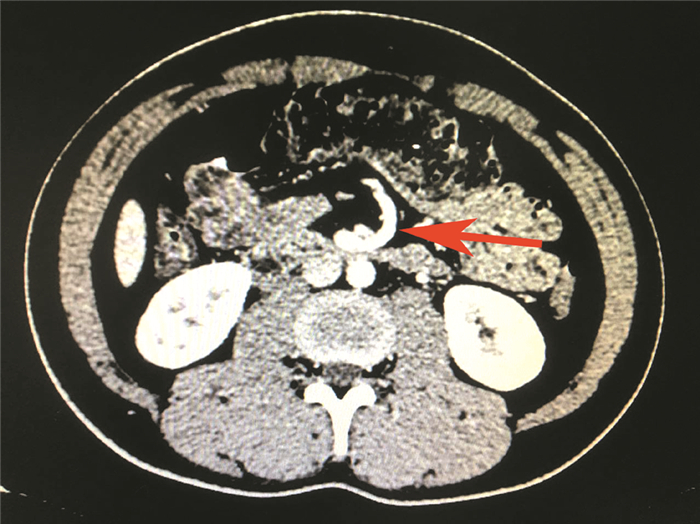

二、实验室及辅助检查血常规、尿常规、粪常规及潜血试验、肝肾功能、电解质、血脂、血糖均无异常。PPD皮试、结核感染T细胞斑点检测以及结核抗体均为阴性。胸部正侧位、腰椎正侧位、腹部立卧位X线检查,肝胆胰脾及泌尿系B超未见异常。上腹部CT加CT血管造影(CTA)示空肠部分旋转至右侧腹,肠曲形态未见异常,肠壁未见水肿;肠系膜上动脉、上静脉分支右旋至右侧腹,旋转角约180°,考虑先天性小肠旋转不良可能性大,见图 1、2。胃镜示慢性非萎缩性胃炎,肠镜示直肠炎症改变。

图 1 一例成人先天性小肠旋转不良上腹CTA 箭头所示为肠系膜上血管分支右旋 |

本例就是通过上腹CT及CTA检查发现空肠部分旋转至右侧腹,肠系膜上动脉、上静脉分支右旋至右侧腹,旋转角约180°,从而考虑诊断成人先天性小肠旋转不良。之后可能由于自动复位,行全消化道钡检时未见异常,患者亦诉腹痛已明显缓解。